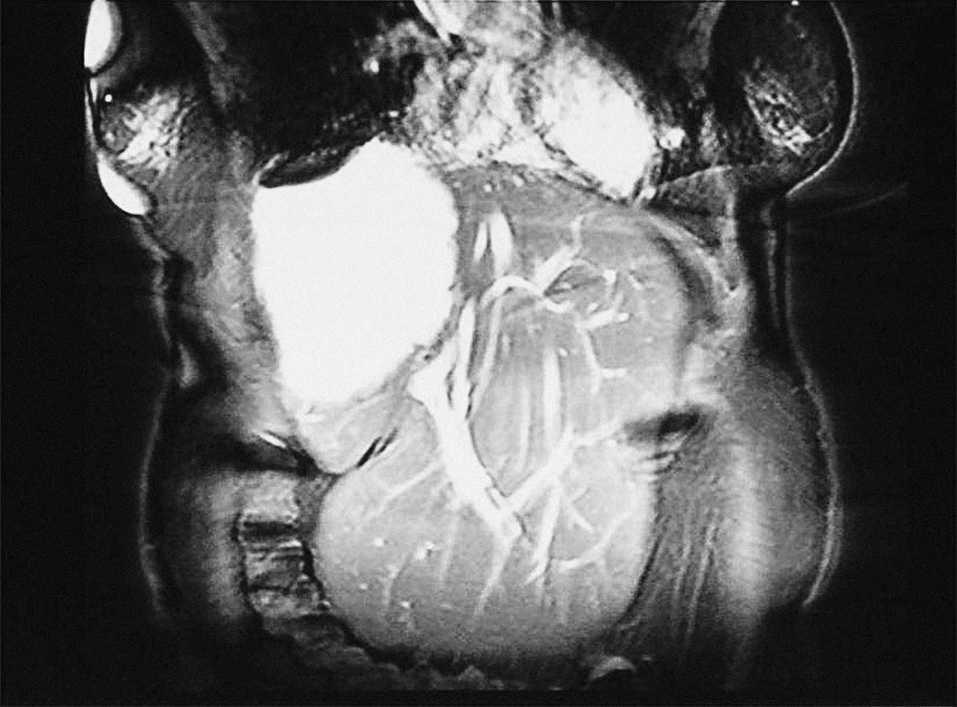

Mujer de 67 años sin antecedentes de interés, que presenta tos irritativa y a la que se detecta una masa hepática en la tomografía computarizada torácica realizada para descartar patología pulmonar. La exploración clínica y la analítica resultan anodinas. La resonancia magnética abdominal demuestra una masa quística hepática bien delimitada, de 15 x 11 x 12 cm, que ocupa todo el lóbulo hepático derecho (fig. 1), con contenido homogéneo, sugestiva de quiste hidatídico, y una hipertrofia compensadora marcada de los segmentos II y III, que miden 20 x 12 x 7 cm (fig. 2 y 3). Se practicó quistoperiquistectomía subtotal abierta. Al año de seguimiento se encuentra asintomática.

Fig. 3.

La hidatidosis, como lesión ocupante de espacio, que puede producir compresión de estructuras vasculares y biliares, es una de las causas de atrofia hepática unilobular. La atrofia y la hipertrofia compensadora tienen implicaciones en el tratamiento de estos pacientes, pues el lóbulo hipertrófico tiende a rotar, y con él lo hace también el pedículo, de manera que las ramas arteriales y las portales se sitúan por delante de los conductos biliares, y dificultan considerablemente el acceso quirúrgico a éstos.